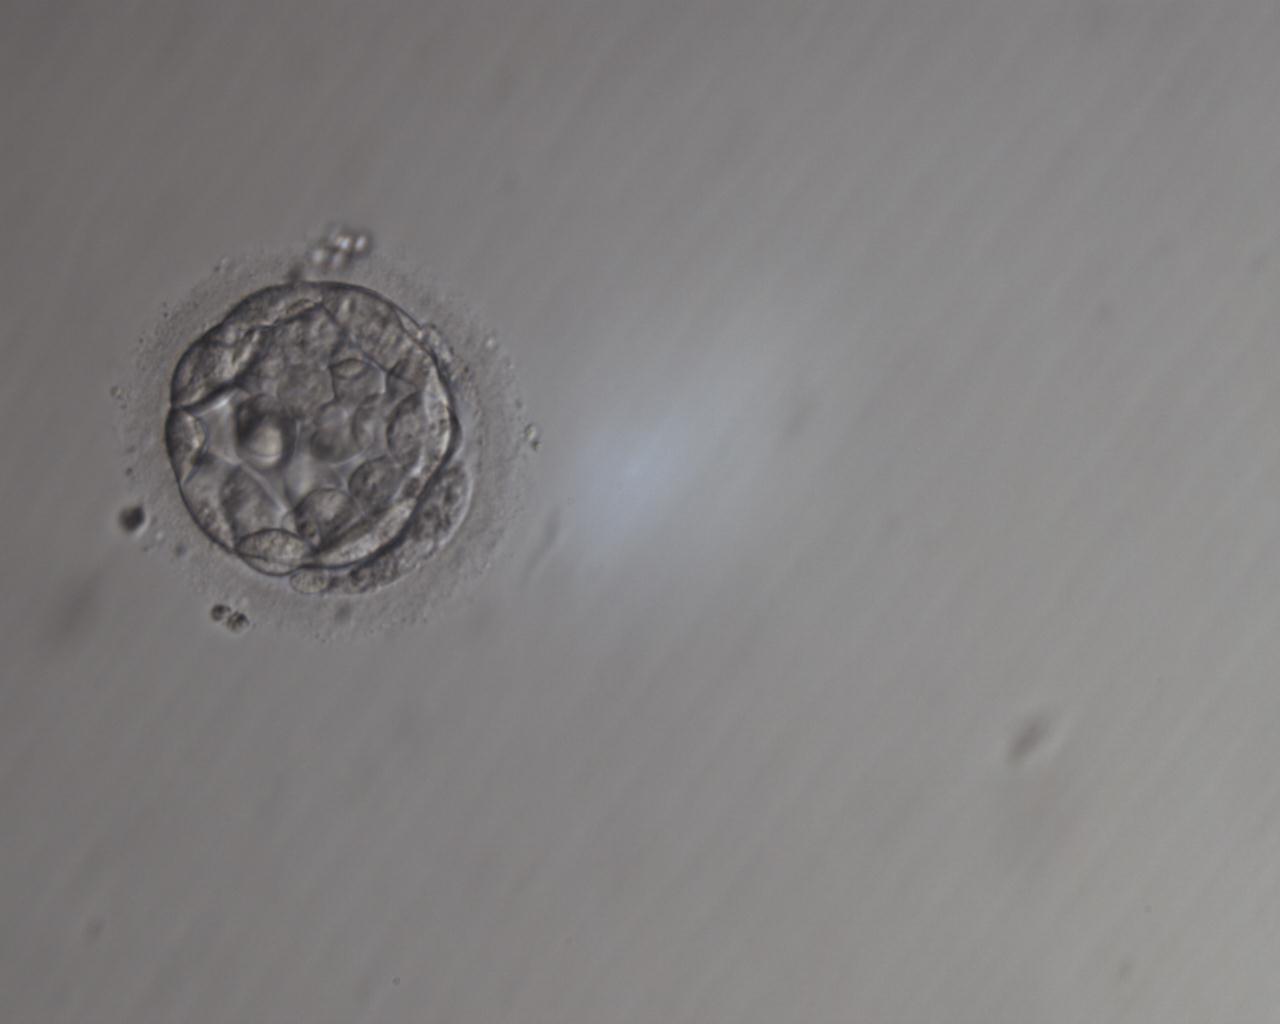

viel Glück mit Ihren beiden Embryonen. Die Vorraussetzungen sind sehr gut, ein Transfer mit 2 schönen BC.

Die obere ist ein bisschen weiter ausgedehnt als die untere, die Strukturen (äußerer Zellring und innere Zellmasse) sind sehr schön ausgebildet und gleichmäßig, die Zona ist zart.

Der untere Embryo zeigt ebenfalls eine gute Entwicklung. Die Strukturen sind noch nicht genau so klar zu erkennen wie bei der ersten BC, der Embryo sieht für diese Phase auch sehr gut aus.